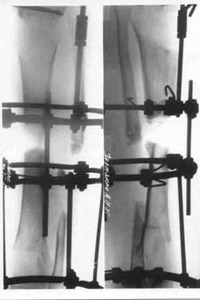

Mechanical treatment of spin-bone by half-spheric mills. |  Osteosynthesis by means of Ilizarov's apparatus. |

| Replacement phase of spin-bone's defect |